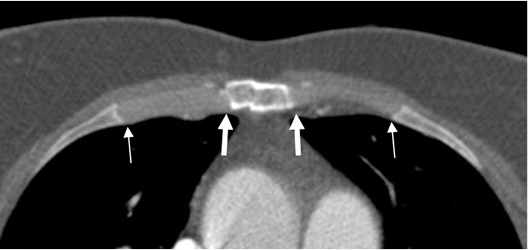

Fig 11. Esternón normal.

TAC axial. Articulaciones costocondrales (Flechas delgadas) y costoesternales normales (Flechas gruesas).